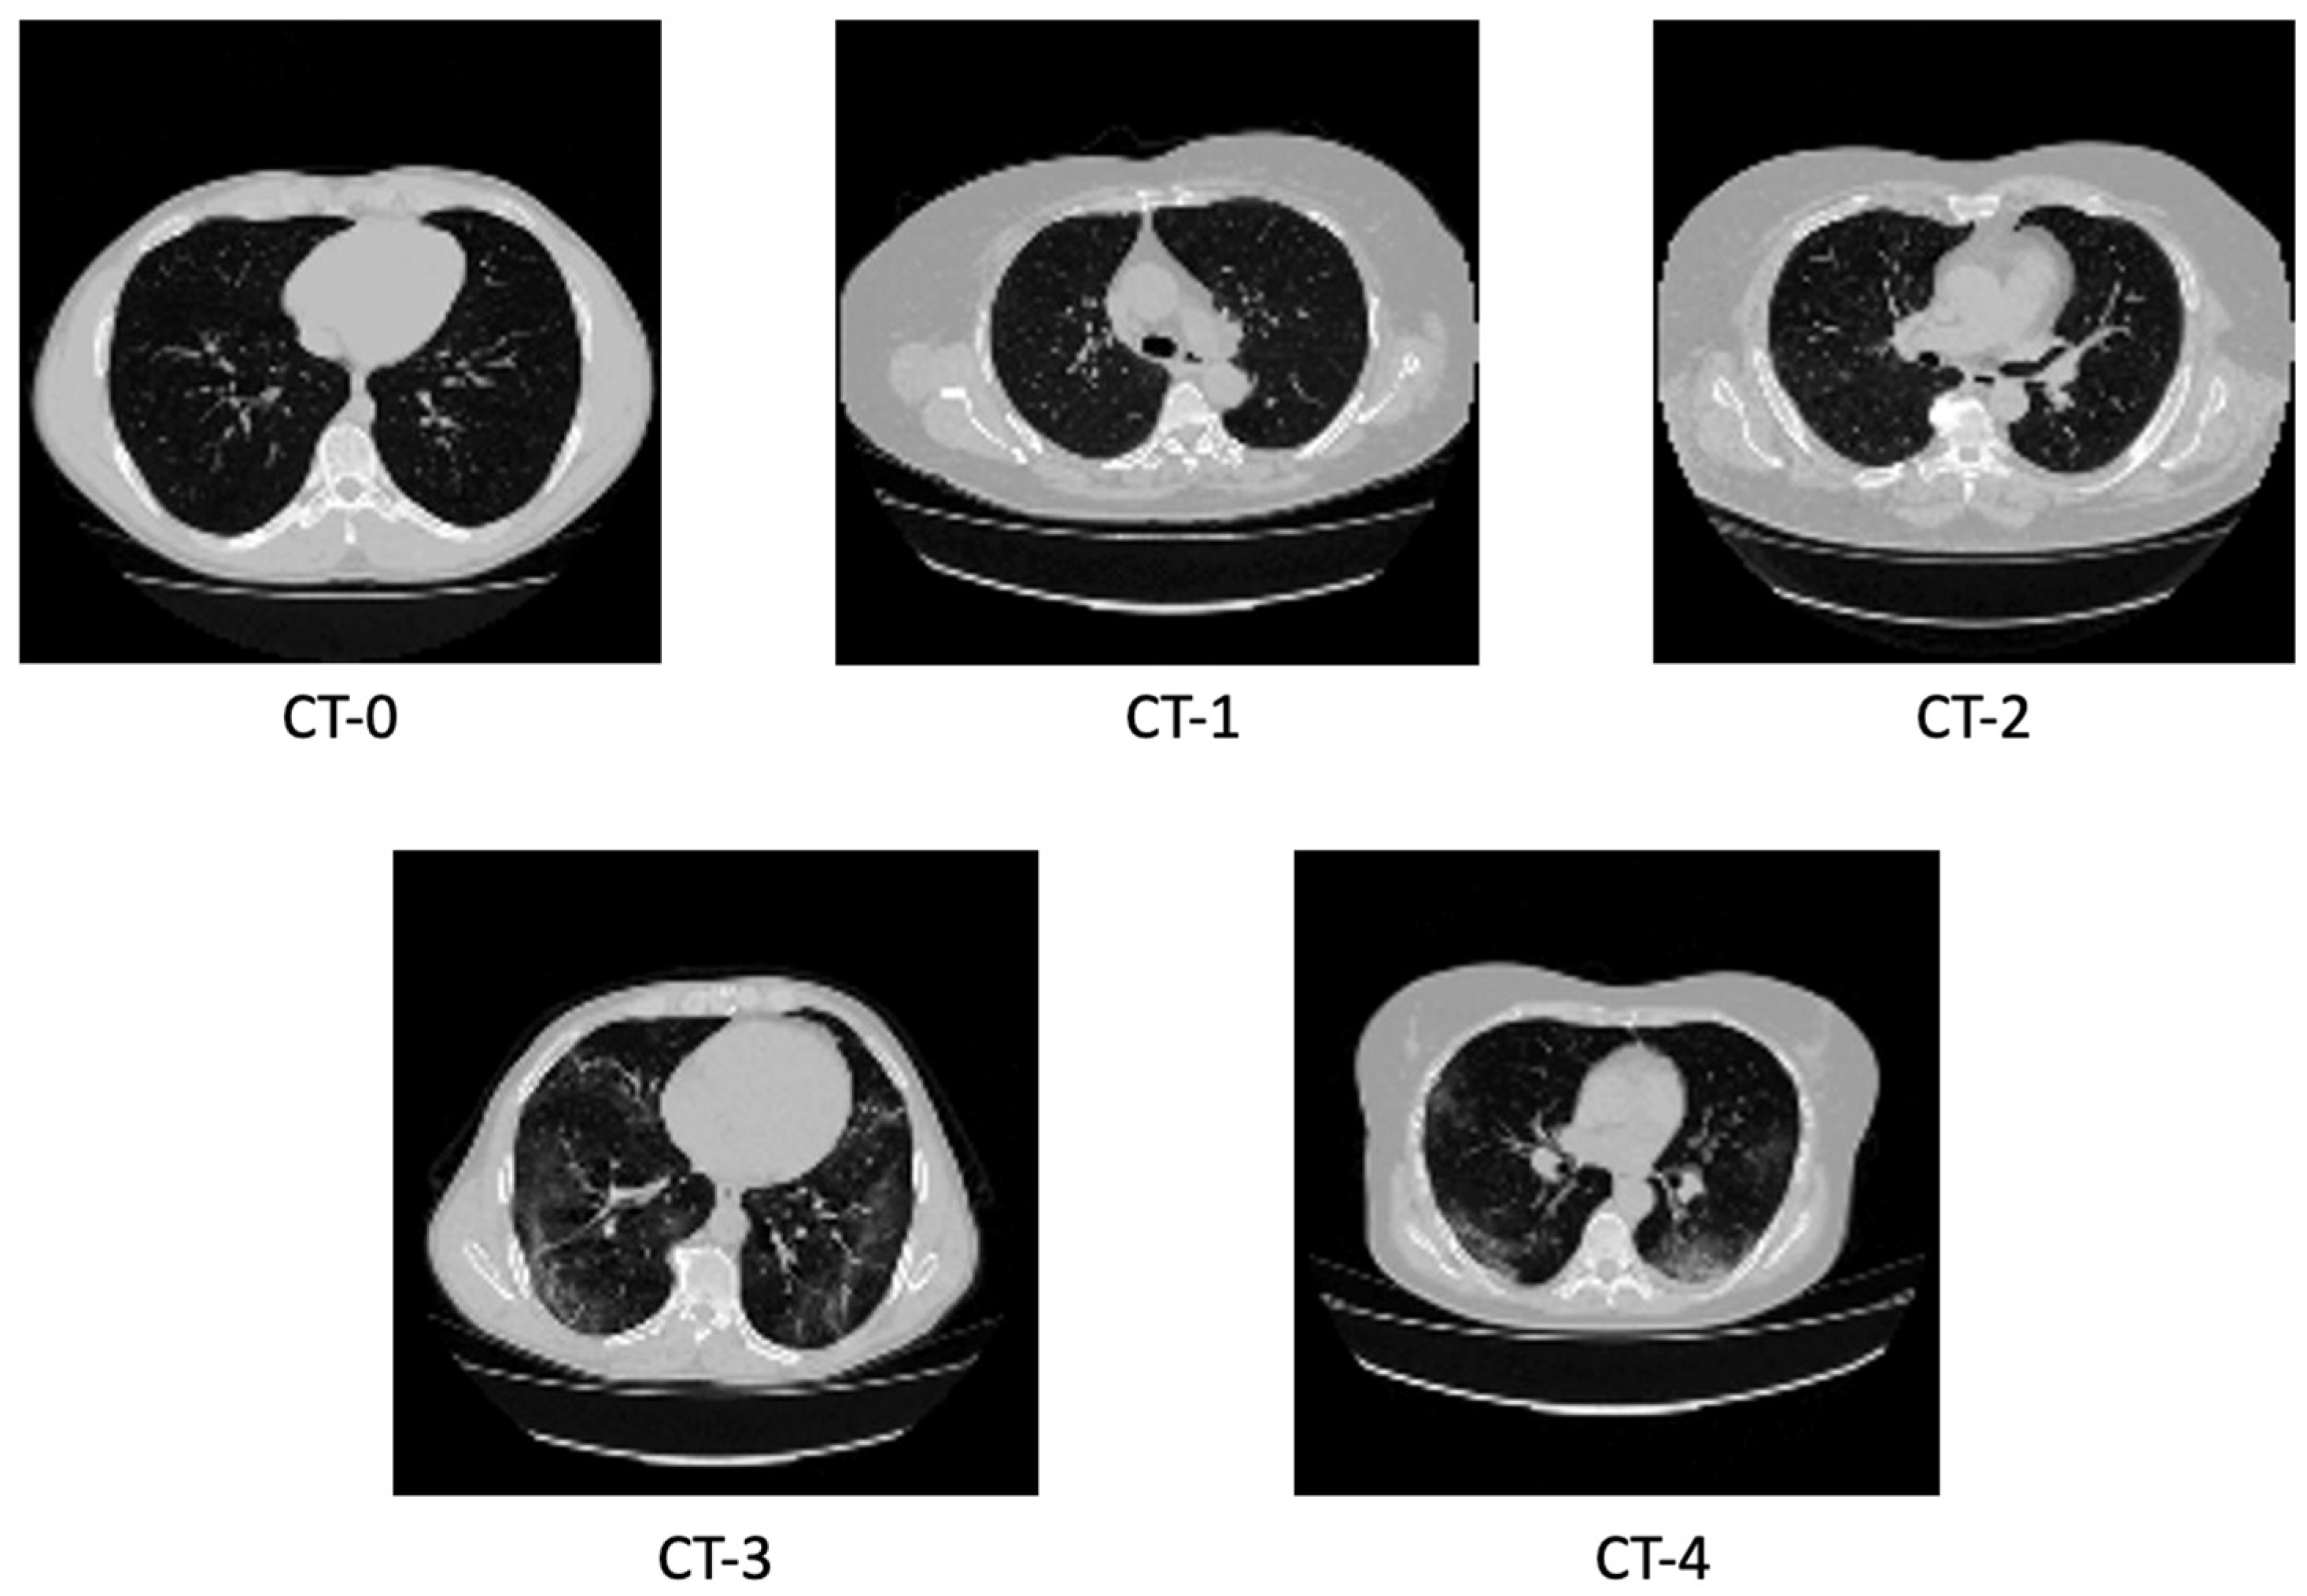

Appendix A

Here, we provide visualizations of different slices from our dataset. We notice that in images with higher CT-levels, it is easier to identify characteristics of COVID-19 like pulmonary occlusions, paving patterns, and ground glass opacities. That said, incremental changes between different class levels are difficult to note, especially between images belonging between class 0 and 1. This illustrates why classifying different images property can be difficult, even for seasoned experts.

Figure A1.

Representation of slices from CTs of different classes.